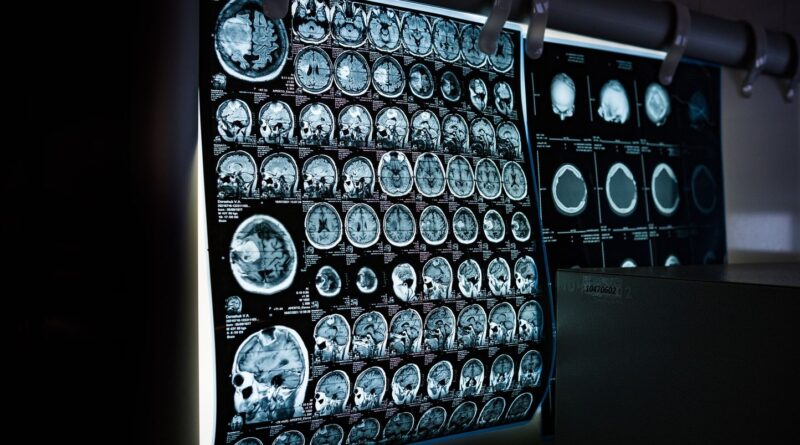

Inquiets, ses parents ont alors interrogé le logiciel d’OpenAI, qui leur a conseillé de consulter un médecin sans attendre. Ils se sont rendus aux urgences où, après de nombreux examens, le diagnostic a été posé : le petit Nyo souffre d’une tumeur située à l’arrière du tronc cérébral, exerçant une pression importante sur son cerveau. Afin de réduire cette pression, un drain a été immédiatement posé pour évacuer le liquide céphalo-rachidien. « Les médecins ont été clairs : en agissant aussi rapidement et en nous rendant immédiatement aux urgences, nous avons sauvé la vie de Nyo. Si nous avions attendu encore quelques jours, il ne serait peut-être plus là aujourd’hui, » a confié sa mère au journal local.

La tumeur a finalement été retirée avec succès le 10 décembre, lors d’une opération de neuf heures. Les tests ont montré l’absence de métastases.

Cependant, bien que l’urgence vitale soit écartée, l’inquiétude demeure. L’enfant n’est en effet pas encore complètement tiré d’affaire. Une IRM a été réalisée pour déterminer s’il reste des cellules cancéreuses ; les résultats, toujours attendus, permettront d’adapter la suite du traitement. En attendant, de nombreuses interrogations subsistent pour ses parents : « Nyo sera-t-il toujours le même ? ». Quoi qu’il en soit, ils souhaitent aujourd’hui faire passer un message clair aux autres familles : « Suivez toujours votre instinct parental. Cela a sauvé la vie de notre fils. »